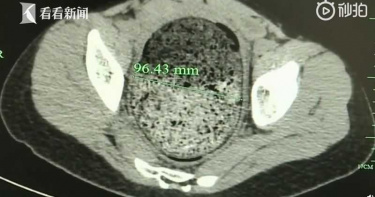

大陸哈爾濱一名22歲嫩妹小王,從小深受便祕困擾,每次進去廁所一待就是30分鐘、1小時,明明肚子脹得難受,卻怎麼樣都拉不出來,上大號沒有一次順暢過,沒想到近來小王便祕的狀況更加嚴重,最久曾30天沒有排便,嚴重影響到生活作息,最後緊急送進手術室治療。根據《看看新聞》報導,小王為了能順利大便,真的是用盡所有招數,不管是服用便秘藥,或是去灌腸,但在這1年以來,情況卻是越來越不妙,她久到1個月都沒有排便,最近3個月還頻頻腹痛,連飯都吃不下,整個人消瘦了近10公斤,嚴重營養不良,肚子也不正常鼓起。(圖/翻攝自看看新聞)近日在家人的陪伴下,小王終於前往醫院就診,哈醫大四院普外科三病房主任劉昶指出,病人剛入院的時候,腹部呈現不對稱性膨隆狀態,且情緒相當焦慮,有慢性中毒的現象,經全面檢查確認,小王罹患了「成人型先天巨結腸症」,最後透過腹腔鏡下全結腸切除術治療。歷經2個小時的手術後,醫療團隊從小王的腹部取出病變腸管,這一幕讓在場所有人都嚇壞,將近2公尺的腸子高度擴張,彷彿是一條「巨大蟒蛇」,其中還積存了大量糞塊,重達10多公斤,相當驚人。如今,順利完成手術並調整飲食後,小王終於能過上正常排便的生活了。